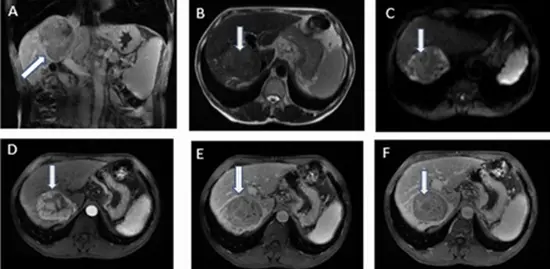

Aim: This study aimed to assess the effectiveness of using MRI-apparent diffusion coefficient (ADC) map-driven radiomics to differentiate between hepatocellular adenoma (HCA) and hepatocellular carcinoma (HCC) features.

Materials and methods: The study involved 55 patients with liver tumors (20 with HCA and 35 with HCC), featuring 106 lesions equally distributed between hepatic carcinoma and hepatic adenoma who underwent texture analysis on ADC map MR images. The analysis identified several imaging features that significantly differed between the HCA and HCC groups. Four classification models were compared for distinguishing HCA from HCC including linear support vector machine (linear-SVM), radial basis function SVM (RBF-SVM), random forest (RF), and k-nearest neighbor (KNN).

Conclusion: The study found that utilizing ADC maps for texture analysis in MR images is a viable method to differentiate HCA from HCC, yielding promising results in identified texture features.